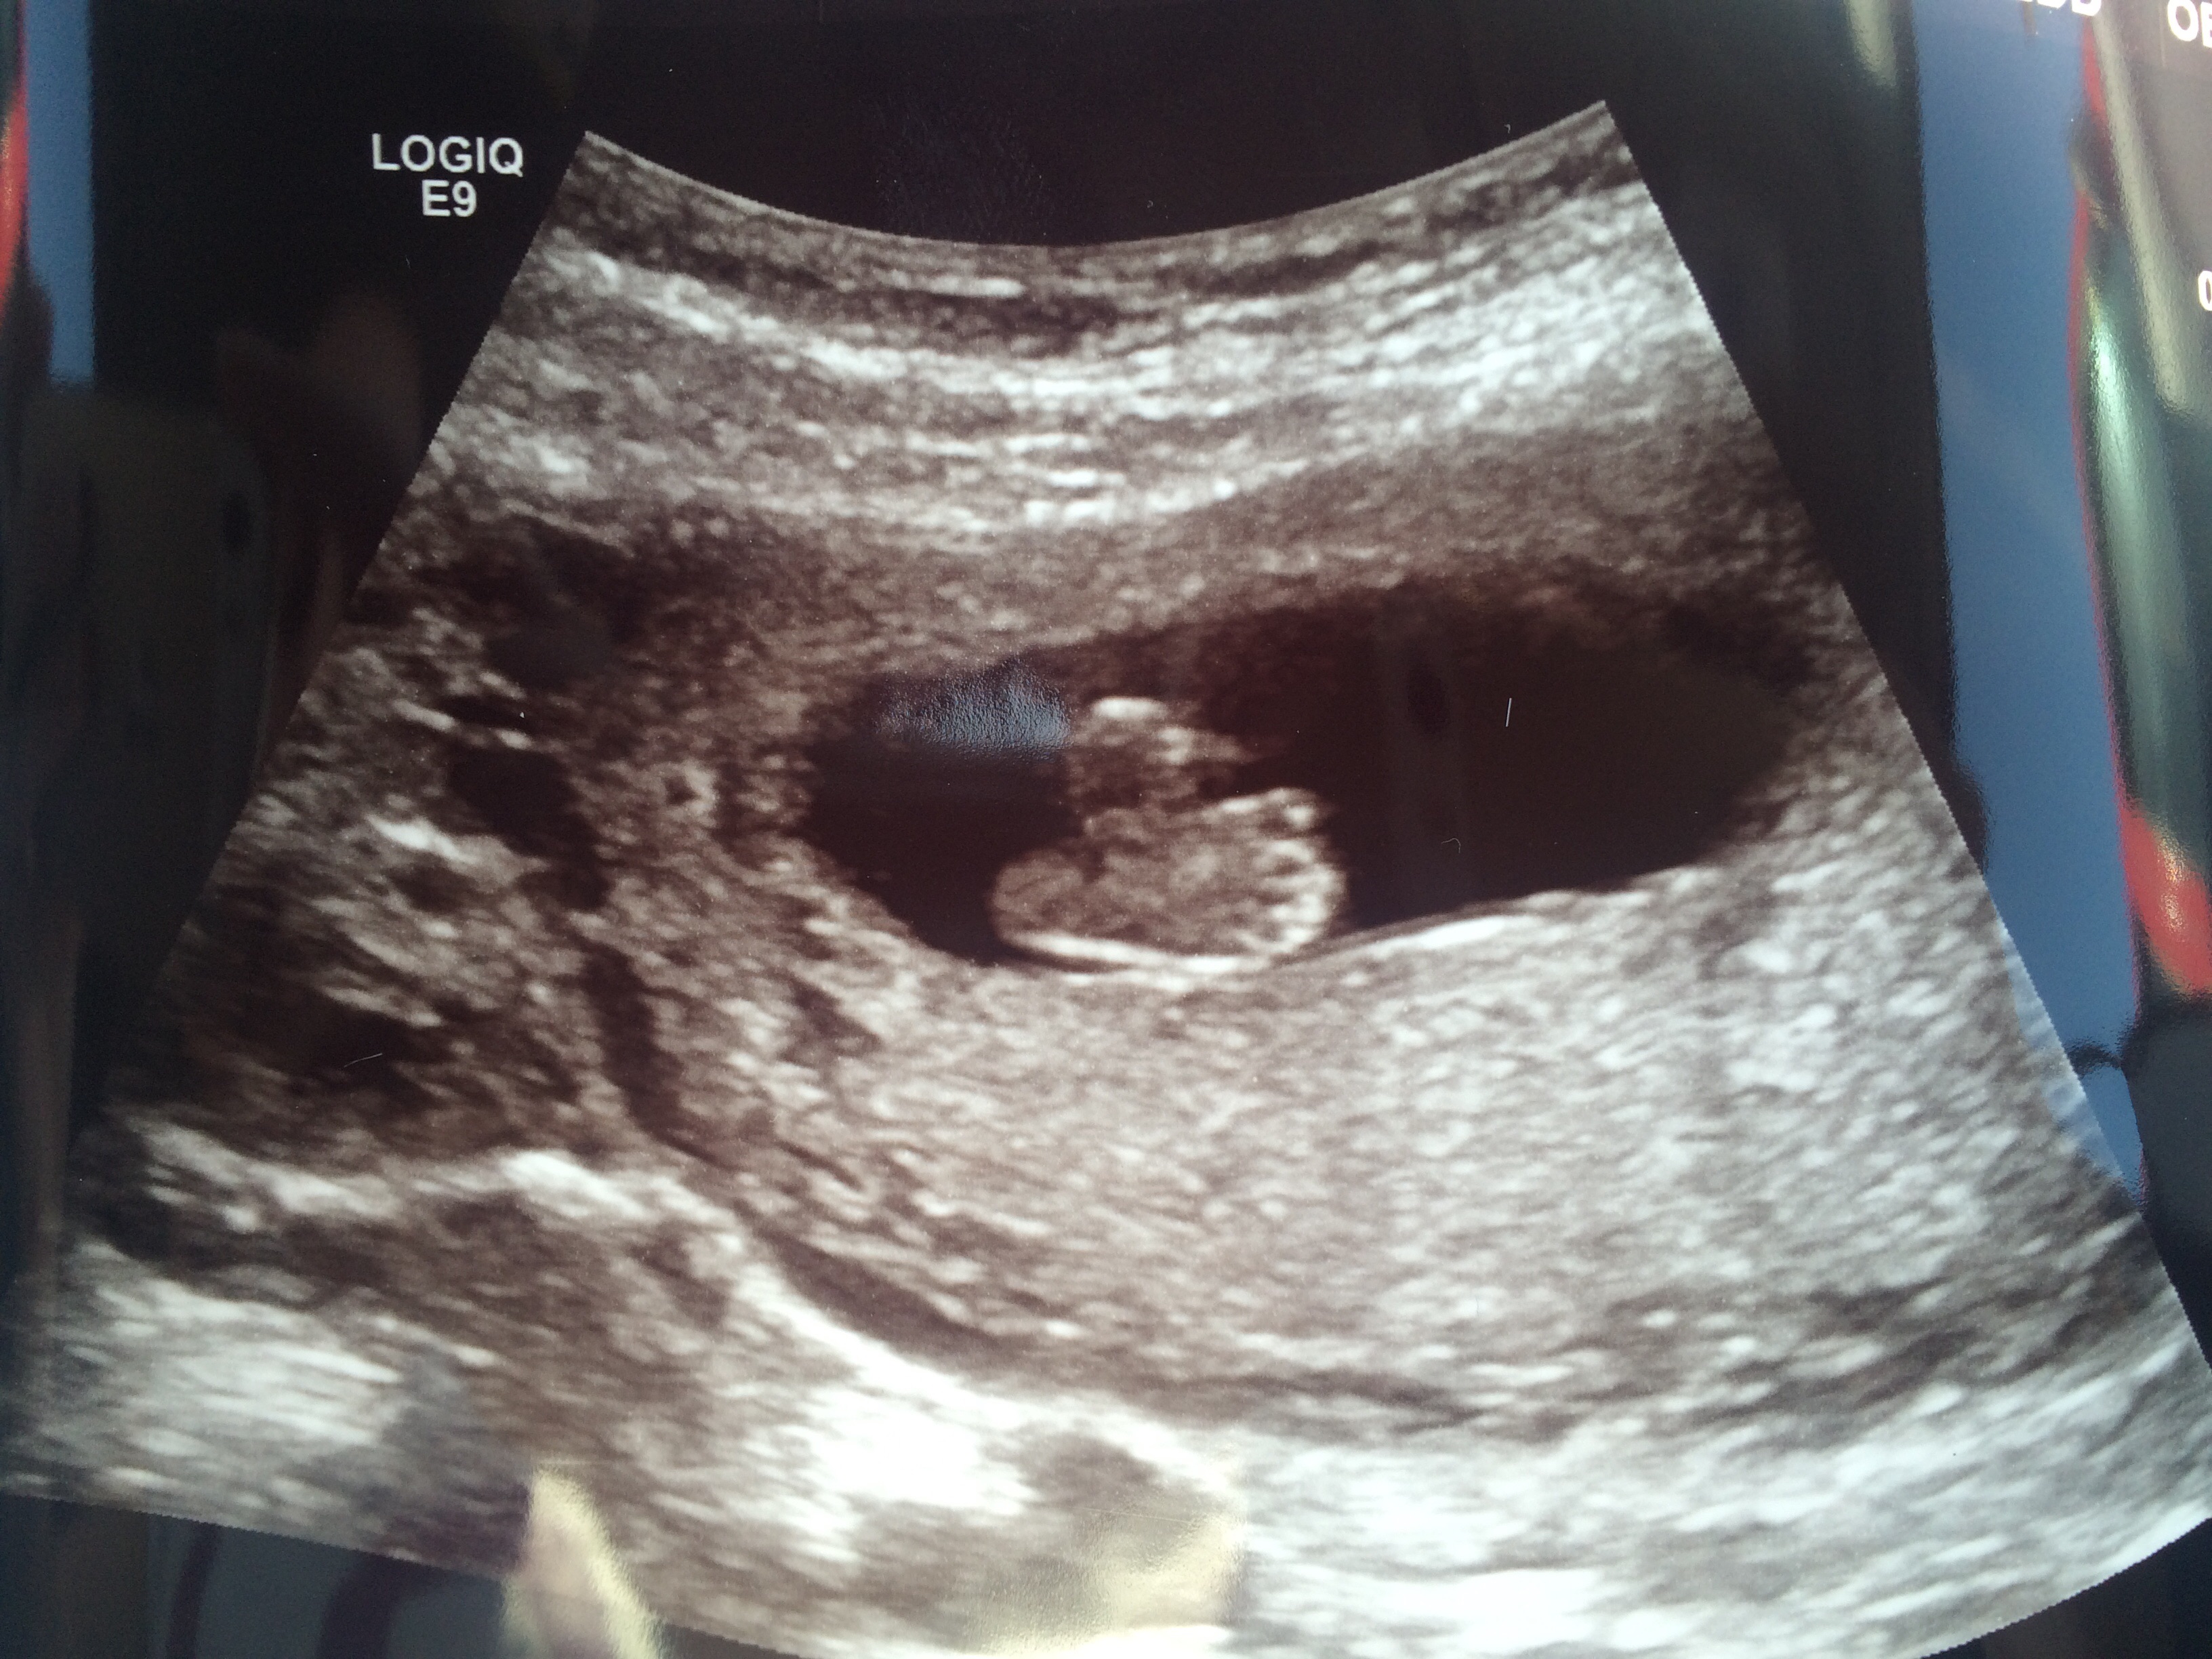

Had our first ultrasound at 9W and got to see our little peanut. We have our anatomy ultrasound in a few weeks to find out the gender. Very excited first time Mommy!